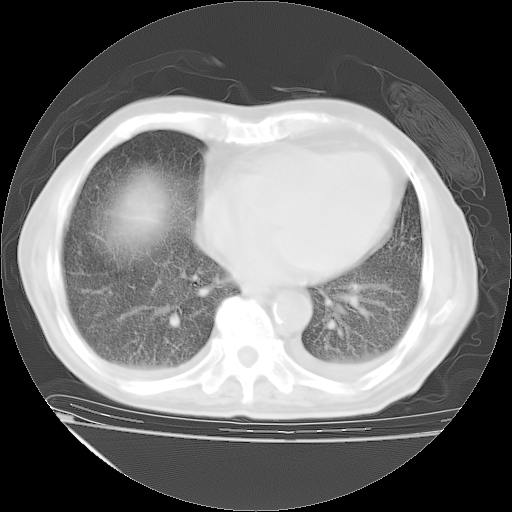

经过24天治疗,岳父的病情基本稳定。生活基本可以自理,可以下床活动。呼吸困难早已消失。体温基本正常。

主要治疗甲强龙80mg×14天,60mg×10天;同时抗结核(异烟肼+利福平+乙胺丁醇)。环磷酰胺0.1 tid 10天。

特别感谢胡教授、高管、桃子版主给出关键的治疗建议。桃版把所有肺部影像和全部临床资料请所在医院呼吸科、感染病科、结核科、临床免疫科专家会诊。临床免疫科专家制定了完整的治疗方案。